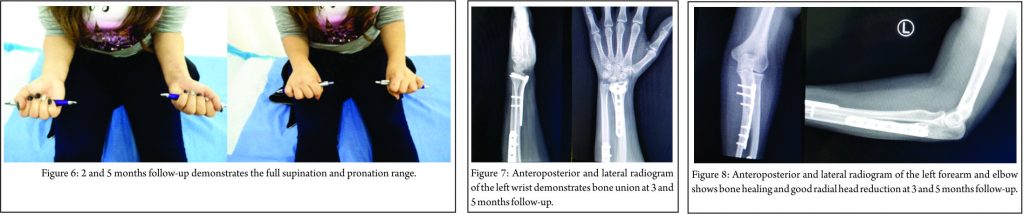

Intraoperatively, after the fixation of both fractures, the elbow was found to be stable in all directions with a full range of motion of wrist, elbow, and forearm. The post-operative course was uneventful, and our patient was discharged 2 days after surgery with a dorsal plaster splint. The cast was removed 2 weeks after surgery, and then gradually the mobilization began. The range of wrist (arc: 108°) (Fig. 4) and elbow (arc: 0–135°) (Fig. 5) motion, as well as the supination and pronation (overall arc: 175°) of the forearm recovered completely 2.5 months postoperatively (Fig. 6).

Roentgenograms and clinical evaluation showed completed bone union of both fractures’ sides 3.5 months after surgery (Fig. 7, 8). The patient returned to her daily routine within 4 months following injury. At last follow-up, 6 months postoperatively, the Broberg and Morrey (98/100) and Quick Dash scores (2.27% of disability) were excellent, without any decline in motion, strength, and stability, accompanied by no pain.